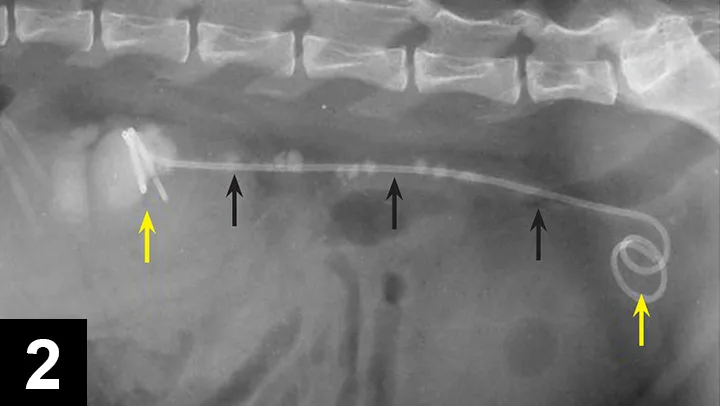

Passive ureteral dilation occurs after stent placement, resulting in dilation of the ureter between 4 and 8 times its normal diameter, which can improve the flow of urine, allow the passage of ureteroliths, or allow the passage of a flexible ureteroscope if necessary. In the author’s practice, ureteral stents (Figure 2) have been placed in more than 300 dogs and cats, with a placement success rate exceeding 95%. It is typically performed endoscopically in dogs and surgically assisted in cats.

Figure 2. Lateral radiograph of a cat with a double pigtail ureteral stent (yellow arrows). The stent is placed next to the large number of ureteroliths (black arrows).